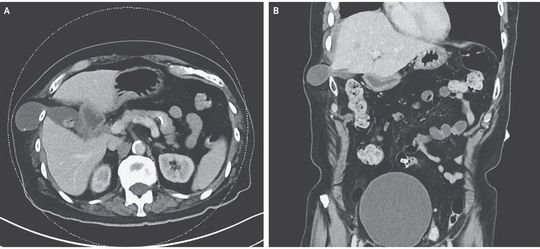

An 82-year-old man presented with a 1-year history of episodic pain and a bulge along the right costal margin. He had undergone a minithoracotomy 4 years earlier for biopsy of recurrent squamous-cell carcinoma in the right lung. Computed tomography revealed transdiaphragmatic herniation of the gallbladder fundus through the seventh intercostal space (Panel A shows an axial view, and Panel B a coronal view). There were no stigmata of inflammation or ischemia, and the hernia size appeared to be stable on staging cross-sectional imaging. Transdiaphragmatic intercostal herniation is a rare occurrence, usually involving the liver, bowel, or omentum, and is most often associated with thoracic trauma. Surgical management requires both diaphragmatic repair and reconstruction of the chest-wall defect. In this case, repair was deferred, given the patient's poor functional status and the minimally symptomatic nature of the hernia. The patient died from complications of widely metastatic cancer 5 months later.